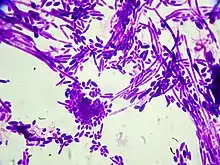

| Gram stain of Candida dubliniensis cells (1000-fold magnification) | |

Candida dubliniensis is a fungal opportunistic pathogen originally isolated from AIDS patients. It is also occasionally isolated from immunocompetent individuals. It is of the genus Candida, very closely related to Candida albicans but forming a distinct phylogenetic cluster in DNA fingerprinting. It is most commonly isolated from oral cavities,[1] and is also occasionally found in other anatomical sites.